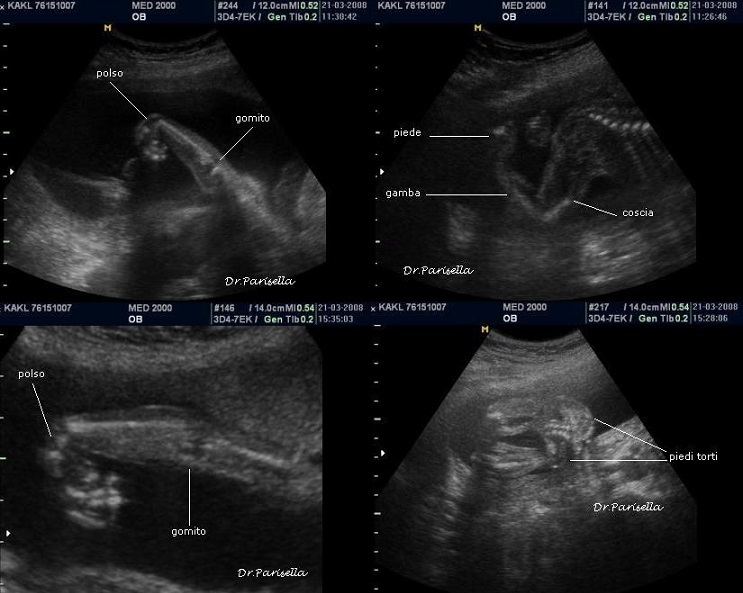

La diagnosi prenatale si basa su:

2) contratture articolari;